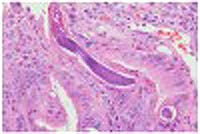

+ Các mẫu bệnh phẩm cũng được xử trí nhuộm haematoxylin và eosin, các mẫu bấm sinh thiết từ dạ dày qua hình ảnh cắt ngang cho hình ảnh nhiều giun tròn (?), hình thể học xác định là S. stercoralis, ngoài ra còn nhìn thấy các hốc, trong biểu mô tế bào tuyến và bên trong lớp lamina propria có phản ứng thâm nhiễm viêm mạn tính;

+ Không có hình ảnh dị sản hoặc tăng sinh của các khối ác tính cũng như có mặt của vi khuẩn Helicobacter pylori; nhuộm haematoxylin và eosin, niêm mạc dạ dày qua hình ảnh cắt ngang của ấu trùng giun lươn Strongyloides stercoralis (xem mũi tên). Các mẫu cắt của tá tràng cho thấy niêm mạc ruột non có cả S. stercoralis. Lớp lamina propria chohình ảnh thâm nhiễm nhiều tế bào viêm mạn tính với nhiều bạch cầu ái toan, bào tương và lymphocytes;